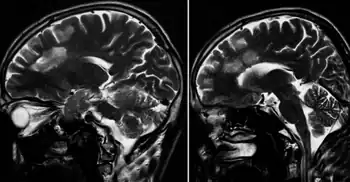

Balo concentric sclerosis -Sagittal T2WI showing confluent hyperintense lesions in periventricular location

Lesions under MRI are distinctive due to their natural concentric shape.

Baló's concentric sclerosis lesions can be distinguished from normal lesions on MRI showing alternating hypointense and hyperintense layers[25]